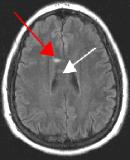

Fig. 1

By turning CSF dark, bright periventricular lesions such as MS plaques become much more conspicuous. Fig. 1 shows a typical T2-weighted axial image of the brain in which CSF in the ventricles appears bright. A lesion on the right is present (red arrow) that is also bright similar to CSF. Fig. 2 is a corresponding FLAIR image showing an obvious bright MS plaque (white arrow) against a background of dark CSF and gray parenchyma with additional more subtle lesions.